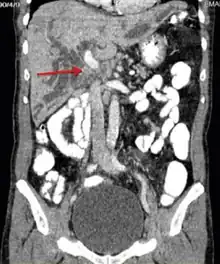

Klatskin tumor

Klatskin tumor, also known as hilar cholangiocarcinoma, is a type of cancer of the biliary tree (cholangiocarcinoma) occurring where the right and left bile ducts join.